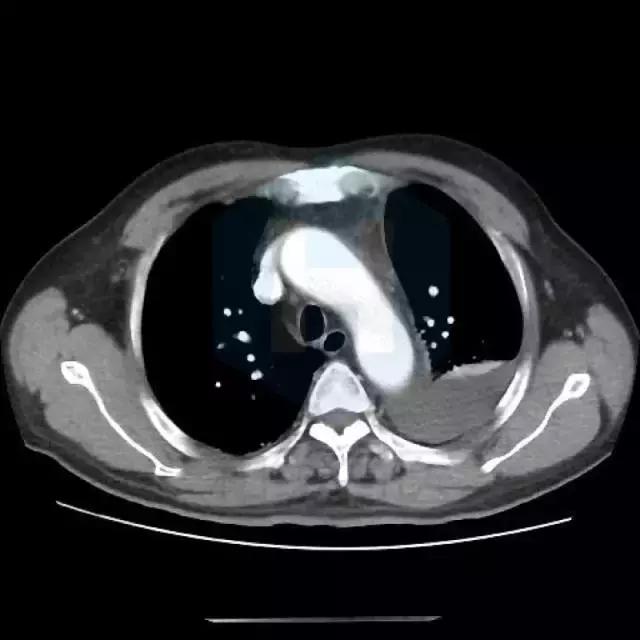

▼影像资料

从CT来看,是比较典型的肺栓塞的表现,应该做肺动脉造影检查。

患者有胸痛,胸闷,1型呼吸衰竭,胸部影像示左下肺为“三角形”肺实变影伴胸腔积液,高度怀疑存在肺栓塞,建议行CTPA检查和肺核素通气/灌注现象检查。同时需排除肺栓塞原因,如肿瘤,自身免疫性疾病等。肺栓塞也会有黄疸和溶血表现。 胸痛特点和表现不符合心绞痛,左侧胸腔积液与左侧肺部病变有关。 患者黄疸考虑为溶血性黄疸,应行查找溶血原因,此外,血红蛋白有下降,便潜血阳性,有同时伴有失血可能,建议查血网织红细胞计数评价贫血情况,应行胃肠镜检查以明确消化道出血原因。 目前低价血症原因考虑不除外副肿瘤综合症可能,关注纠正电解质紊乱。 可视医院条件,建议安排下一步检查:胸部增强CT及CTPA,或肺通气/灌注检查,下肢及深静脉超声,血肿瘤标志物,血网织红细胞计数,自身免疫抗体(ANA,ENA,ANCA)等,胃肠镜检查。 由于目前有消化道出血风险,暂不建议抗凝治疗。密切观察。